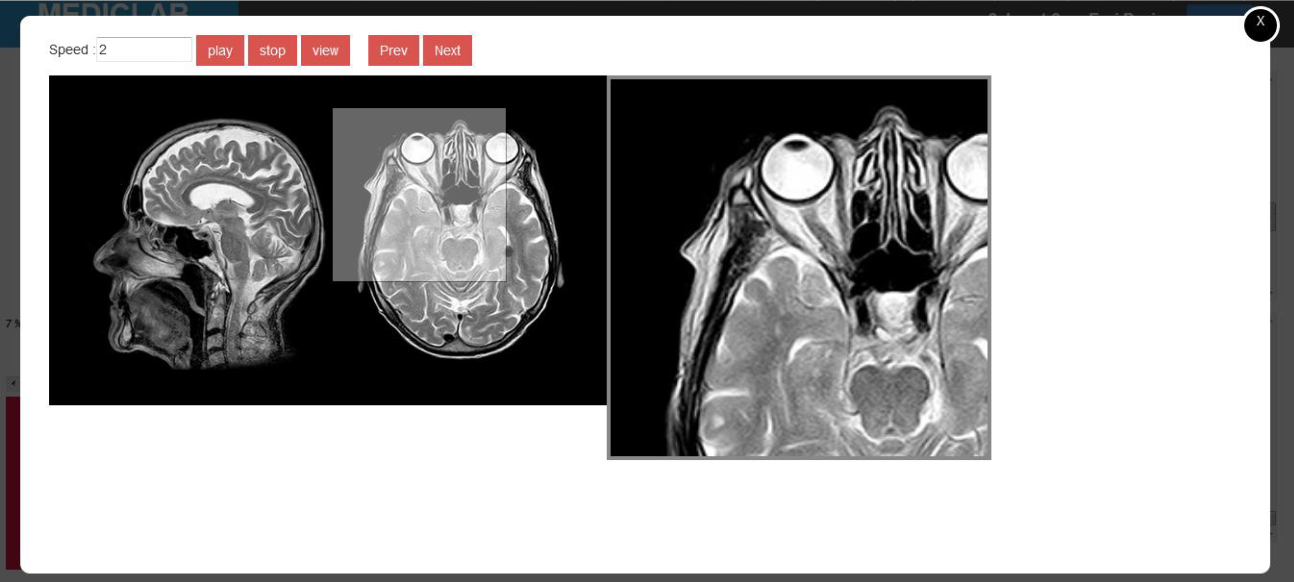

RADIANT Radiology Intelligence Analyser System

Enigmed Radiant is special complex radiology system that will give you advice,prediction,control and total analysing result with laboratory result Our artifisual intelligence will analyse and give advice the situation realtime